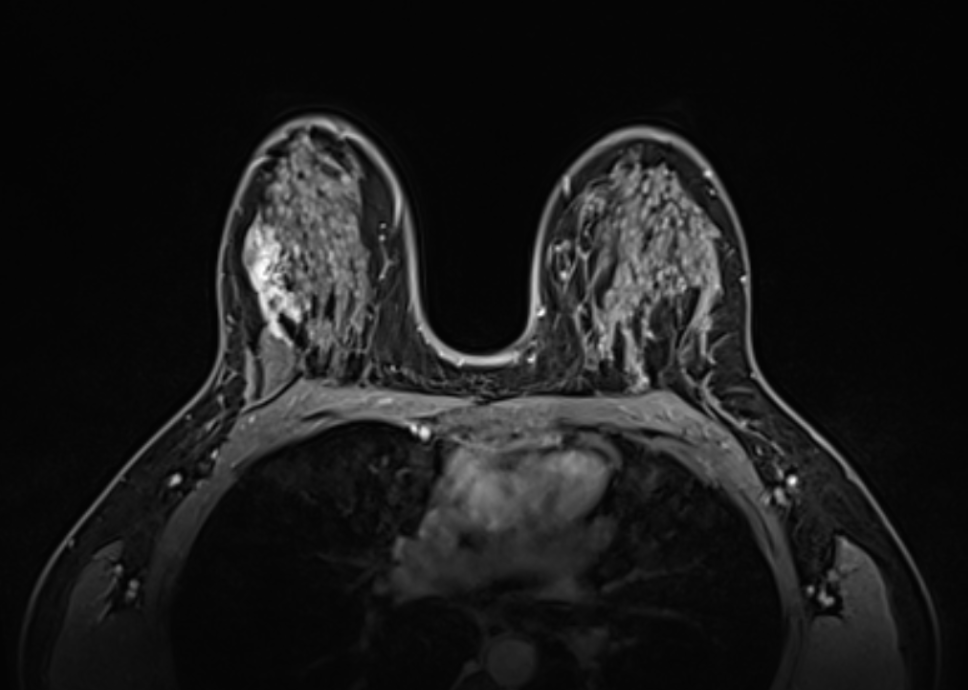

Հաջորդիվ իրականացվել է ռենտգեն մամոգրաֆիա և կրծքագեղձի ՄՌՏ հետազոտություն:

Հետազոտությունների արդյունքում՝ բուժառույի մոտ ախտորոշվել է աջ կրծքագեղձի տարածուն DCIS (կրծքագեղձի ծորանային կարցինոմա in situ)

Այնուհետև կատարվել է ստերիոտակտիկ վակումային բիոպսիա, ռենտգեն մամոգրաֆիայի հսկողությամբ ,որի արդյունքում ախտորոշվել է աջ կրծքագեղձի ինվազիվ կարցինոմա: